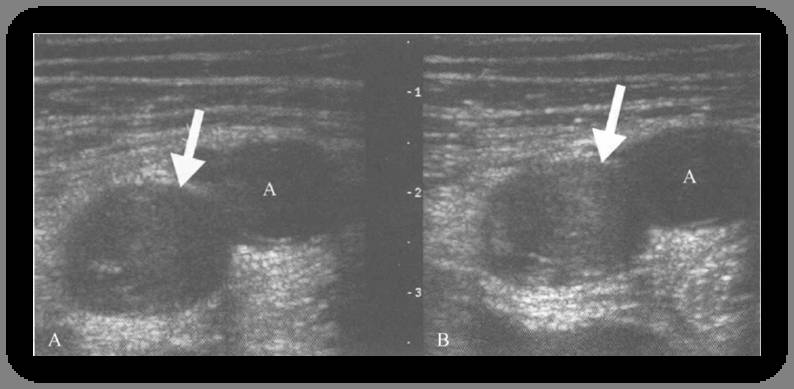

D-二聚体检测筛查上肢DVT疑似病人不被推荐。压迫性超声检查是首选的影像检查,尽管上方的骨性结构常常妨碍近端锁骨下静脉及头臂静脉的观察。在9个研究的回顾中,压迫性超声检查诊断上肢DVT的敏感性97%,特异性96%。如果碰到远端静脉通畅而怀疑近端静脉(锁骨下和头臂静脉)病变时,观察多普勒的频谱形态,包括变异性减低、valsalva动作后血流速度无变化。也有一个研究表明,彩色多普勒和压迫性超声想比较,并不能提高诊断的准确性。下图为压迫示意图和下肢DVT压迫试验的图例。